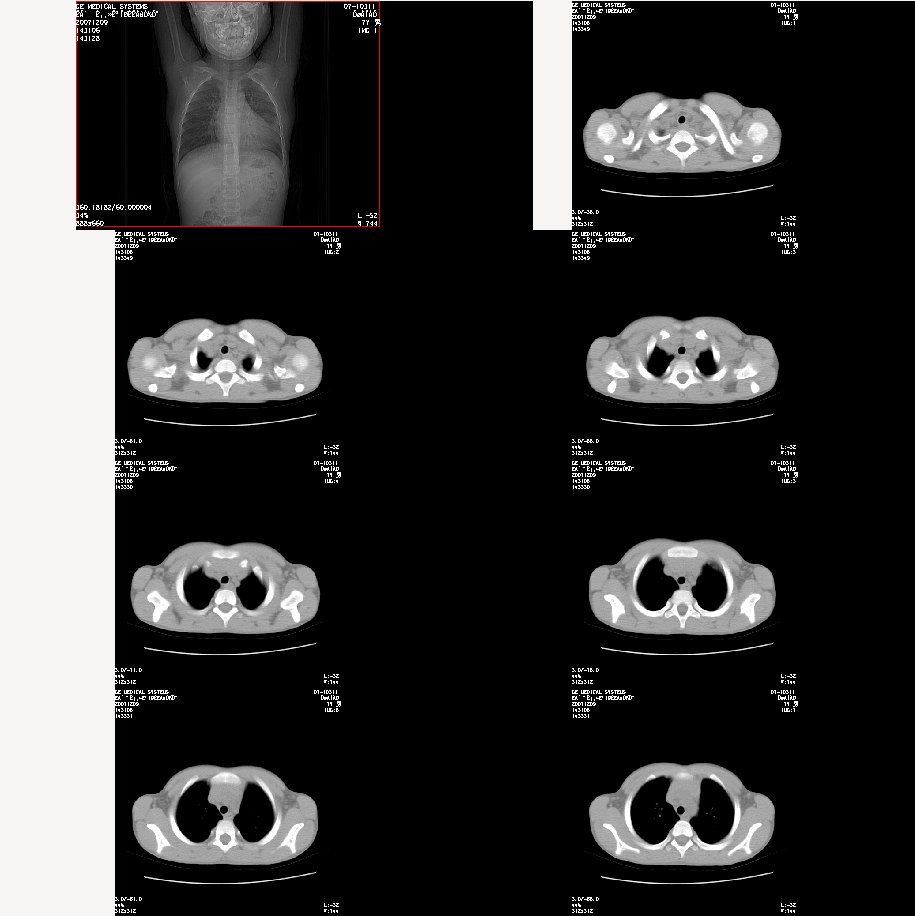

m 7

咳嗽、咯血半月。查体:双肺呼吸音粗,可及干湿鸣。自诉每年均有发作。